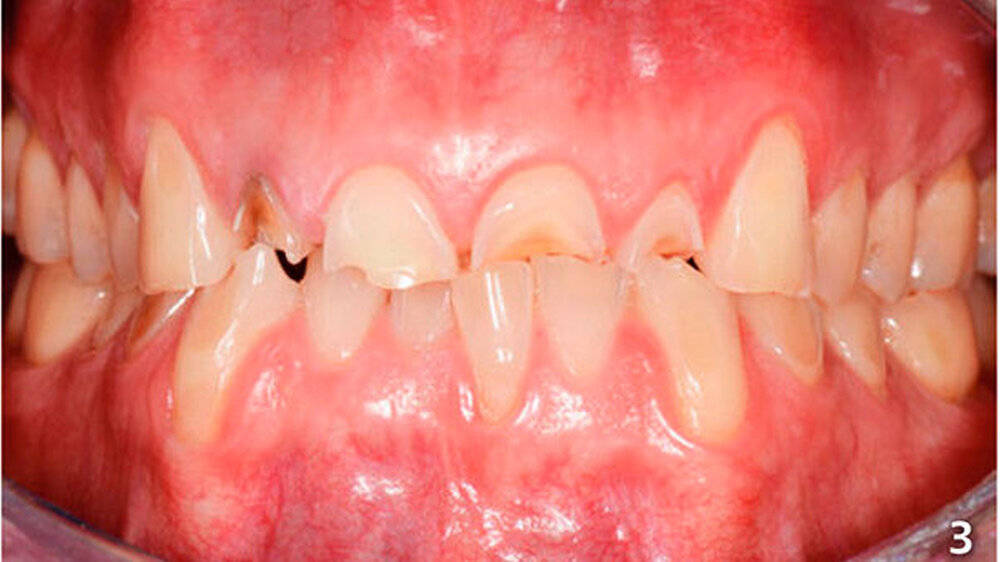

Der Patient wies an allen Frontzähnen sowie an den Seitenzähnen des Unterkiefers starke erosive Defekte auf (Abb. 1-3). Der Patient störte sich vor allem am Erscheinungsbild seiner Oberkieferfrontzähne und dem Engstand im Unterkiefer-Frontzahnbereich. Er wurde über verschiedene Therapiemöglichkeiten ausführlich aufgeklärt und entschied sich für direkte Rekonstruktionen mit Komposit. Im Februar 2016 erfolgte die Versorgung mit Kompositrestaurationen, wie folgt beschrieben.